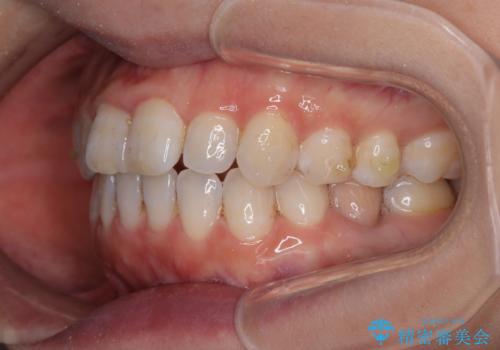

【モニター】飛び出した上顎前歯 補助装置を併用したインビザライン矯正治療

- 上下前歯が非接触となり、前方に突出していることを気にして来院された患者様です。

上下の前後差が大きいため、インビザライン単独での上顎歯列移動は困難と判断し、補助装置により上顎歯列を後方移動させ、その後インビザラインにて仕上げていくこととしました。

補助装置なしでも改善できる可能性はありましたが、補助装置で確実性を上げ、短期間できっちりと仕上げることができました。